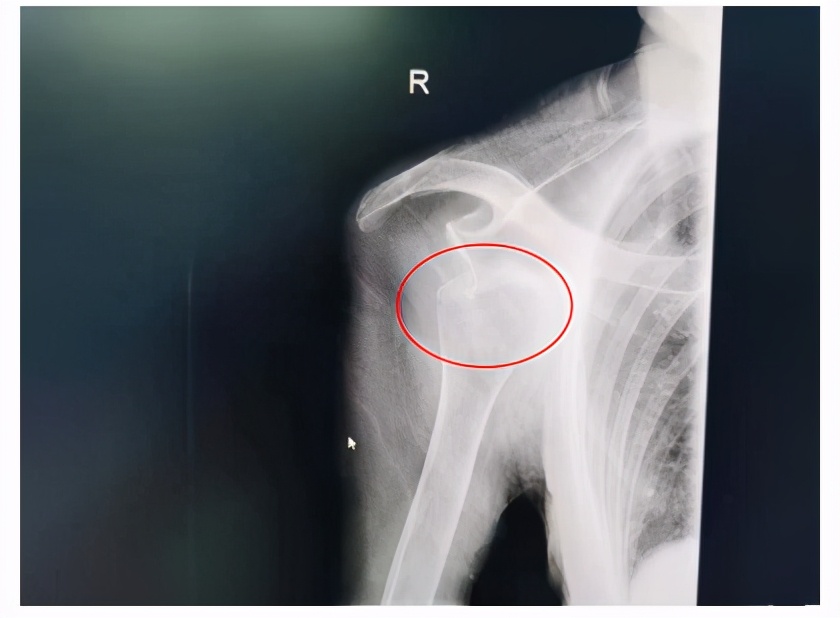

肩关节脱位X光片

吴向阳副主任医师介绍,肩关节是人体最灵活的关节,也是全身最不稳定的关节,跌倒等间接*力暴**容易导致肱骨头脱离肩胛骨的关节盂而引起肩关节脱位,肩关节脱位约占全身关节脱位的1/2。像刘奶奶这样的脱位在医学上称之为前脱位,在日常生活中较为常见,约占肩关节脱位的85%,而并发症可高达21%。